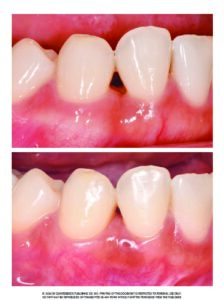

矯正治療の後や歯肉炎の後に、歯と歯の間にポッカリと空いてしまう「黒い三角形のすき間」。これを専門用語 ...